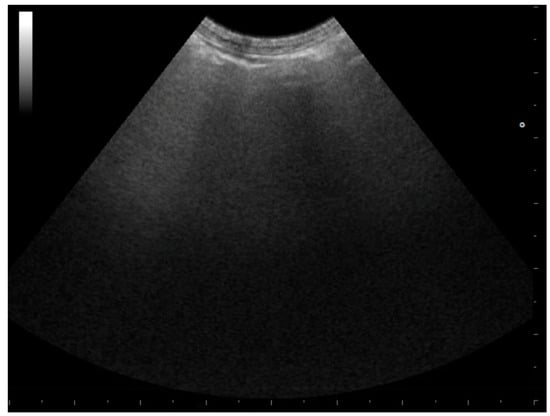

3.1.1. Pneumothorax